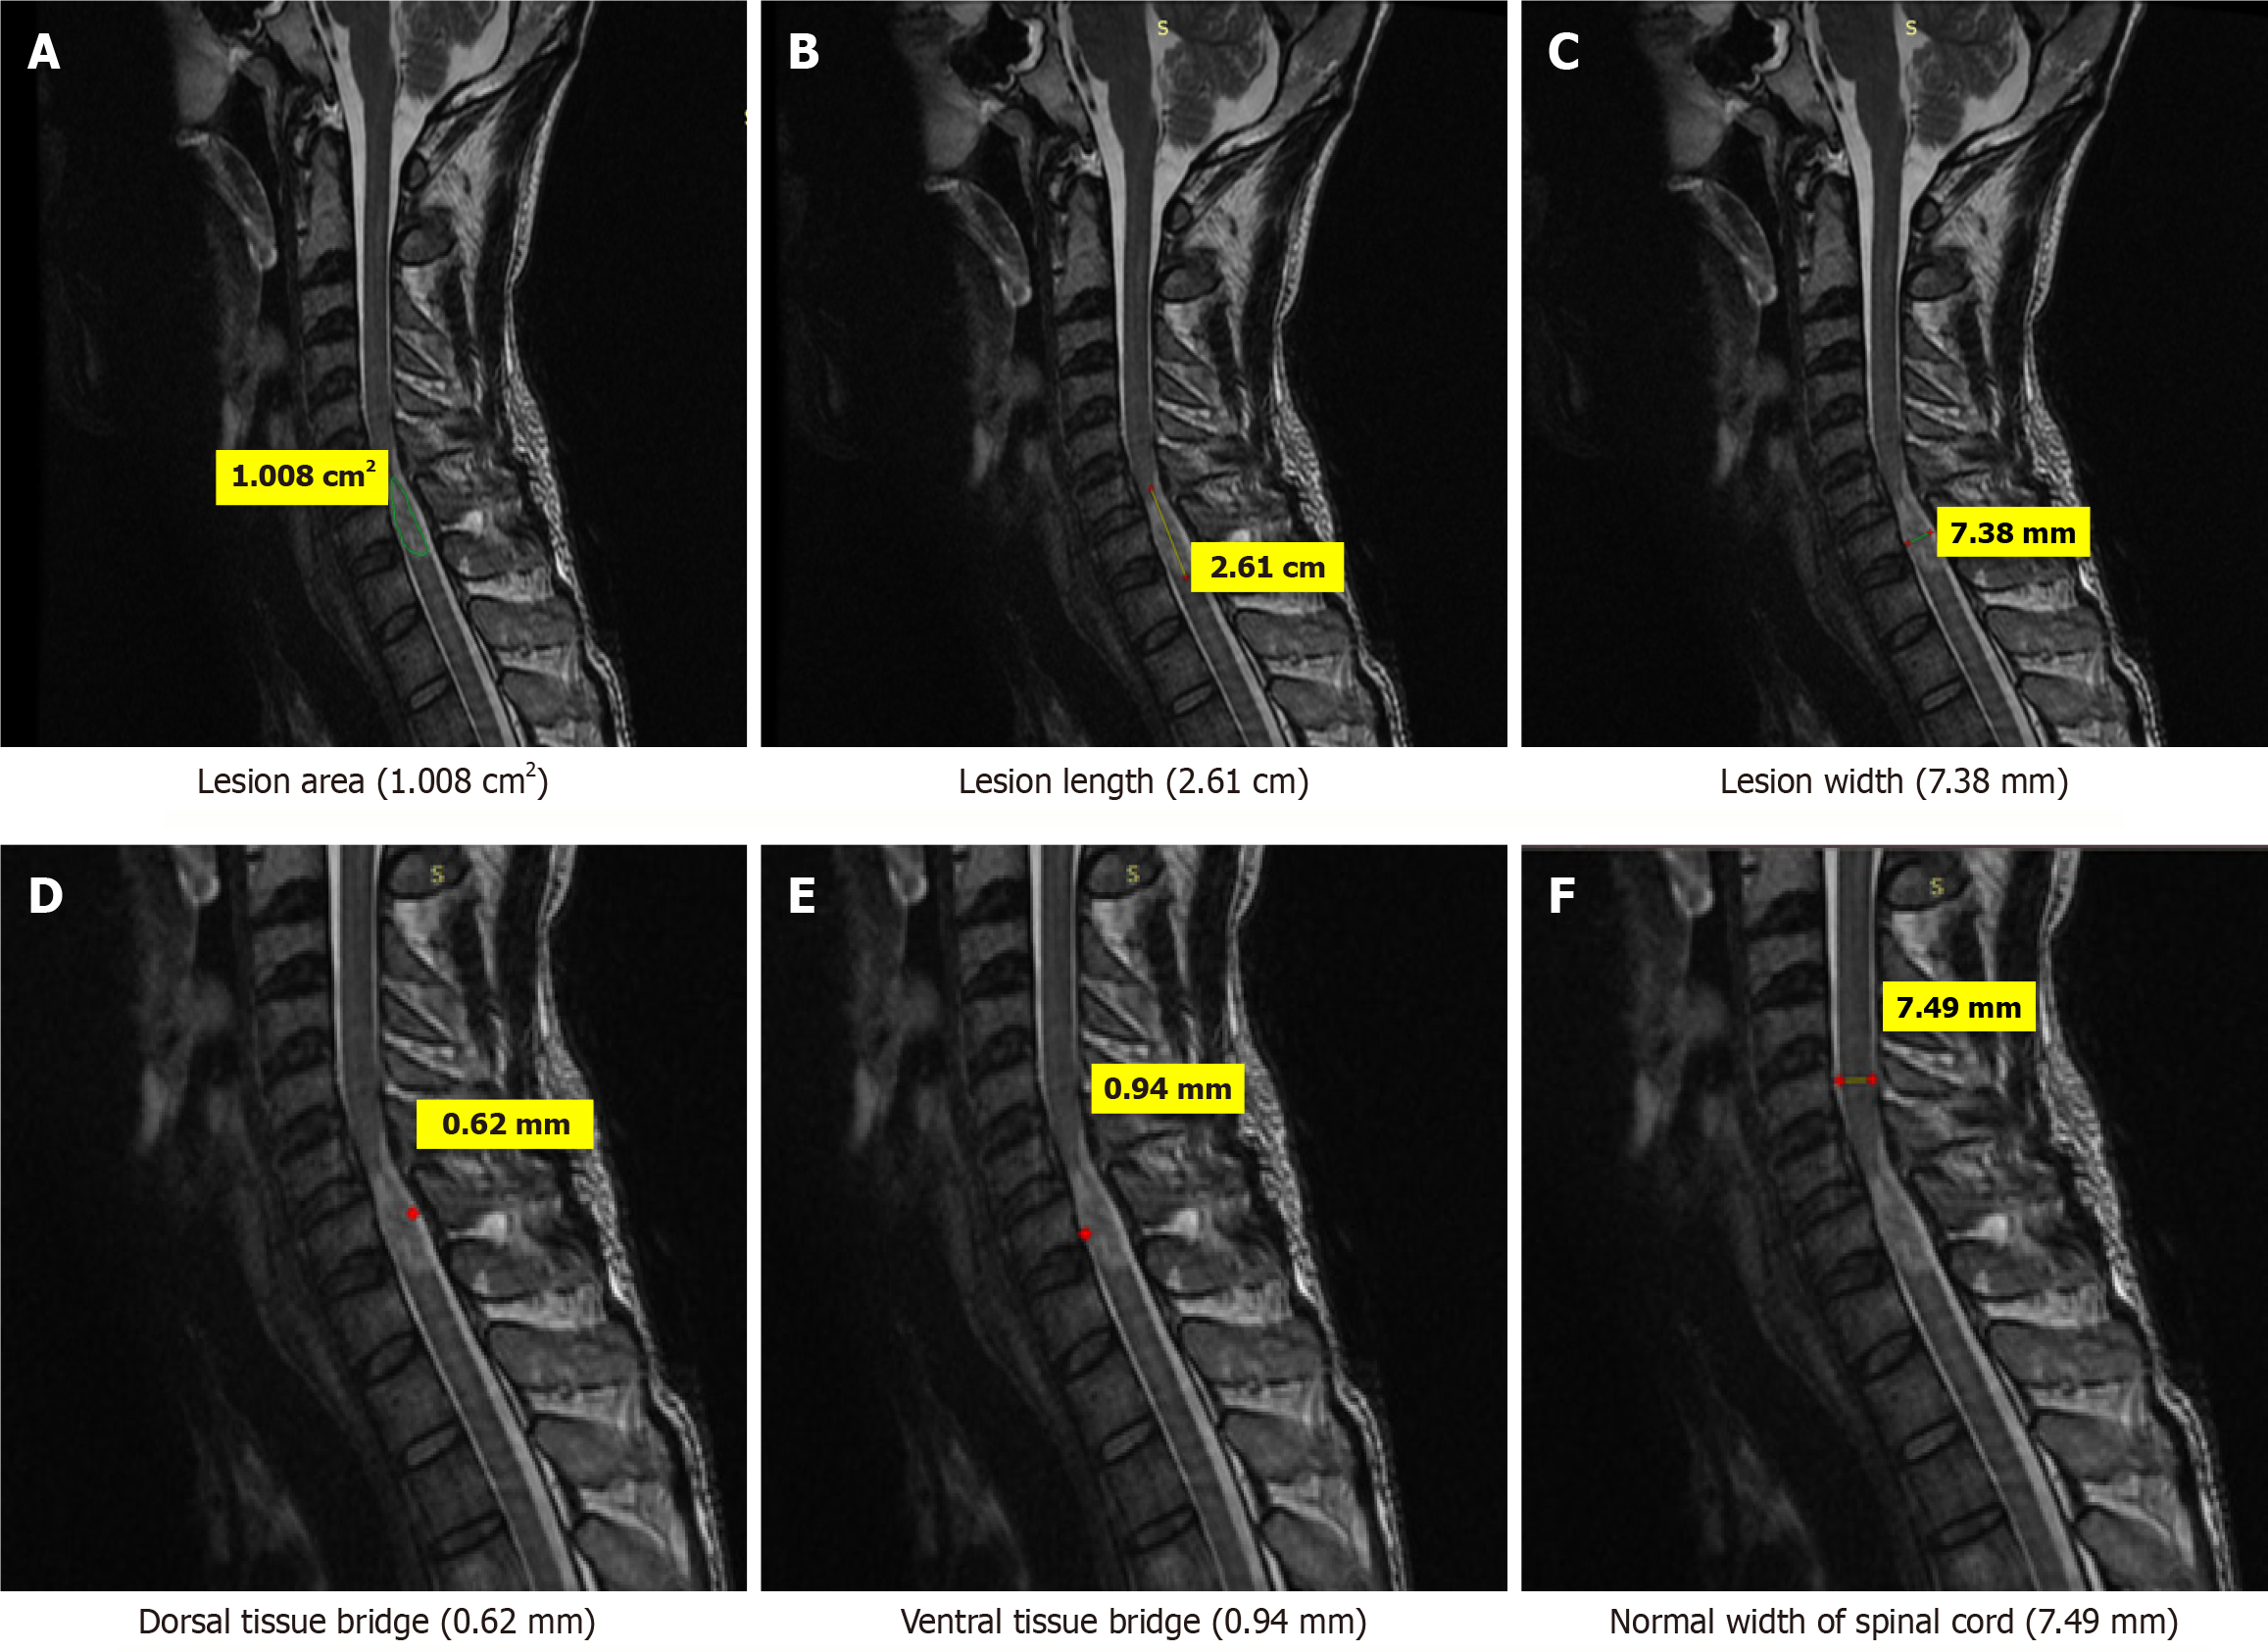

Figure 3 Magnetic resonance imaging T2-weighted sagittal images of a 39-years old patient who sustained trauma of cervical spine (C5-C6) with ASIA grade D.

A: Lesion area (1.008 cm2); B: Lesion length (2.61 cm); C: Lesion width (7.38 mm); D: Dorsal tissue bridge (0.62 mm); E: Ventral tissue bridge (0.94 mm); F: Normal width of spinal cord (7.49 mm).